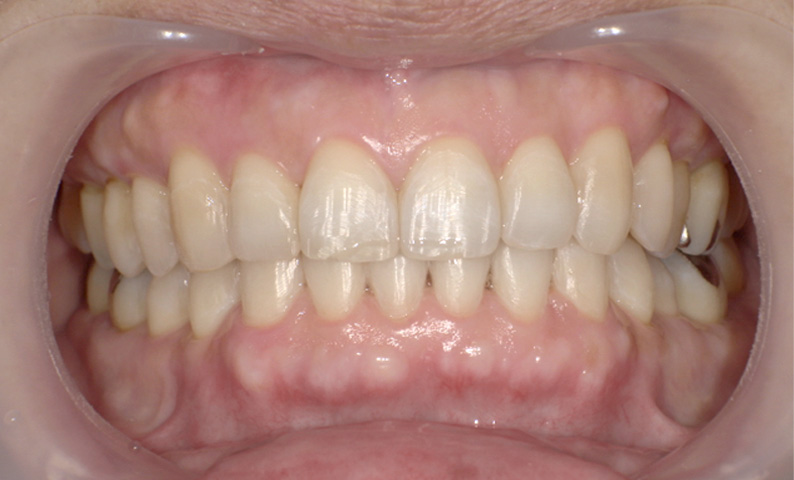

症例:上下顎の部分矯正

症例_007 「出っ歯」症例

治療期間:9ヶ月金額:54万円+税60代女性出っ歯捻転歯